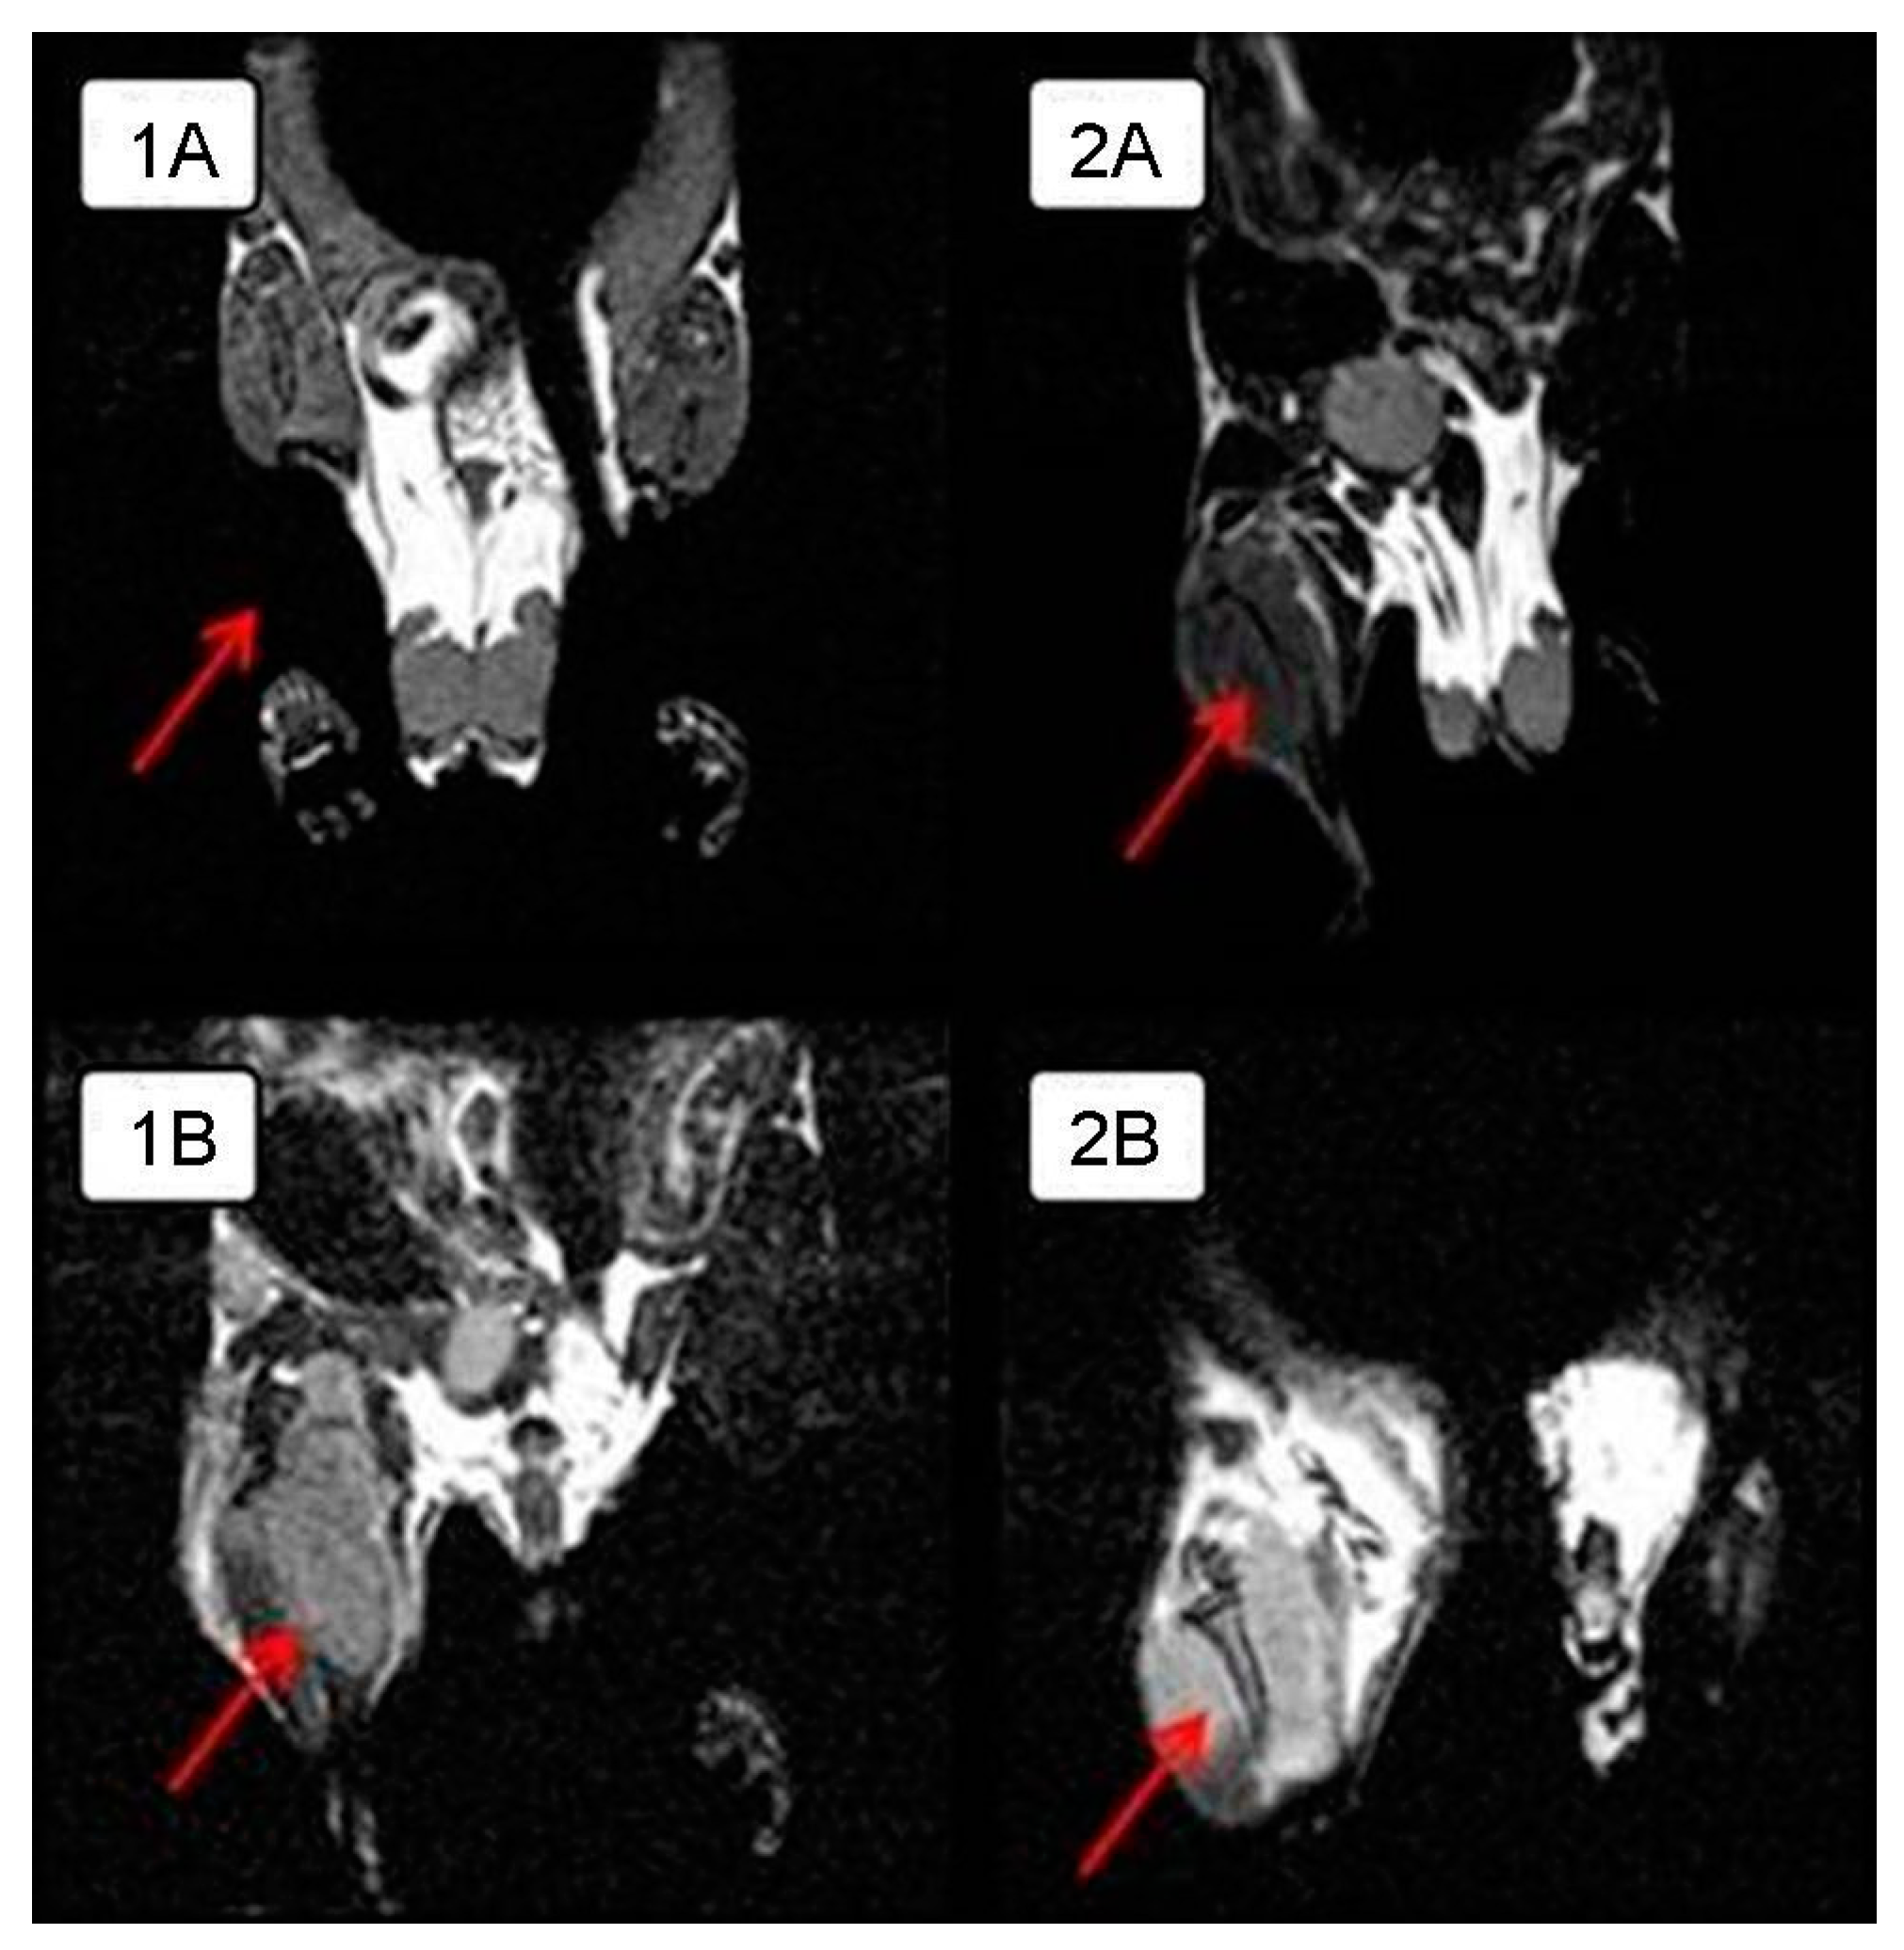

In order to visualize the tumor node growth in detail in the control group and compare the differences in the size of the intramuscular tumor with those of the experimental group animals, MRI was performed on day 28 of the experiment. The tumor is clearly visualized next to the normal tissues in a series of frontal sections on MRI. The obtained MRI data revealed almost complete tumor regression in one experimental mouse and a significant tumor reduction in another mouse compared to the control animals (Figure 2); intramuscular thigh tumor is clearly visualized next to the normal tissues.

Figure 2.

MRI of intramuscular Krebs-2 solid tumor nodes in BALB/c mice in the frontal plane on day 28 from the onset of the experiment. Arrows indicate the tumor. A. Experimental mice receiving intratumoral injections of NDV/Altai/pigeon/770/2011 at a dose of 256 HAU per 100 μL for 5 days: (1A)—complete tumor regression compared to the control animals, (2A)—significant tumor reduction compared to the control animals; (1B,2B)—control mice treated with saline injections.